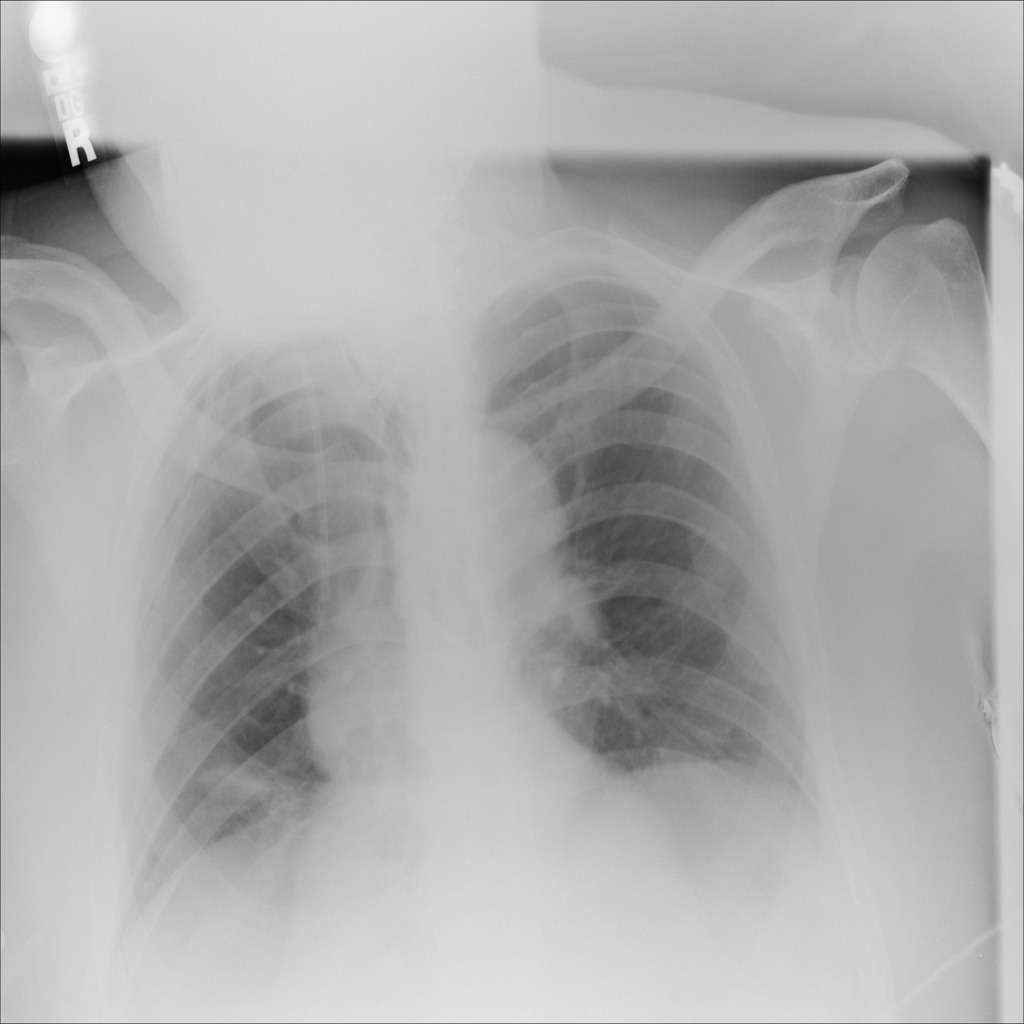

PAT-DB80 · IMG-000Atelectasis

PAT-DB80 · IMG-000

PA